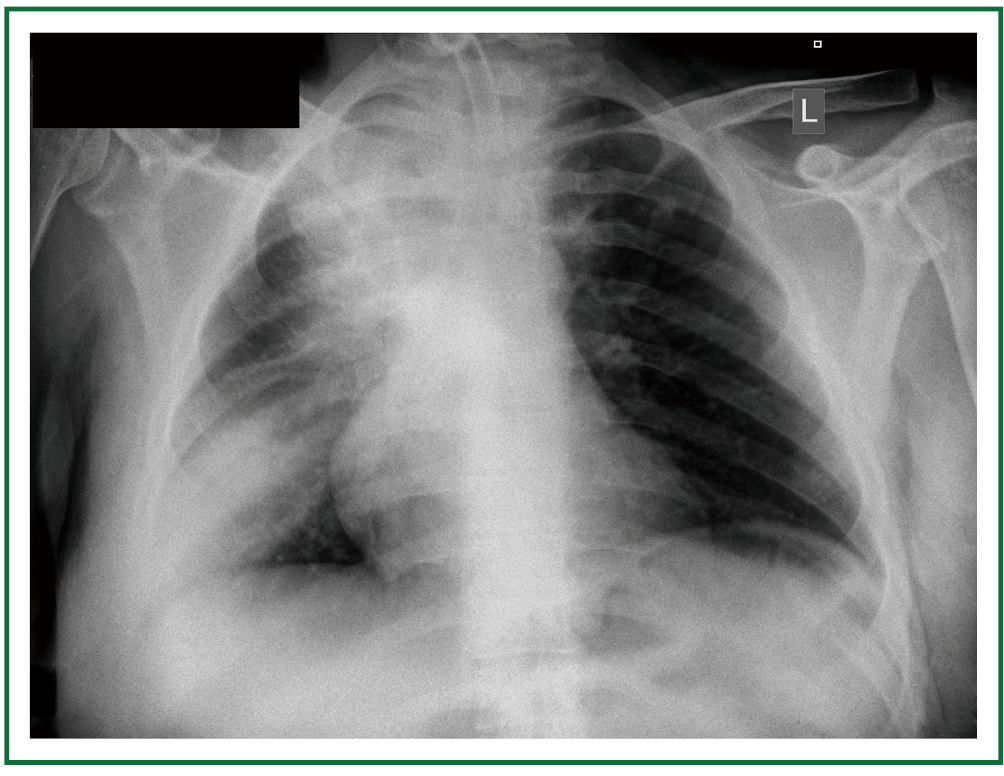

Tracheostomy tube x ray. The present study was conducted to evaluate the utility of post tracheostomy x rays. The width of the tube diameter should be 23 rd of the tracheal width and the cuff should not distend the tracheal wall. Length cuff resting mm mm mm o mm 4 dct 4 50 94 62 20 6 dct 6 64 108 74 24 8 dct 8 76 122 79 27 10 dct 10 89 138 79 29 ref. Assoc prof craig hacking and dr aditya shetty et al.

It should lie parallel to the trachea. A full length x ray marker allows the position to be checked easily. Adult tubes are usually approximately 1 cm in. Tubes come in a variety of sizes and have a balloon at the tip to ensure that gastric contents are not aspirated into the lungs.

The tip of the tracheostomy tube should be half way between the stoma and the carina at the level of the d3 vertebra. Evaluation of endotracheal tube position.